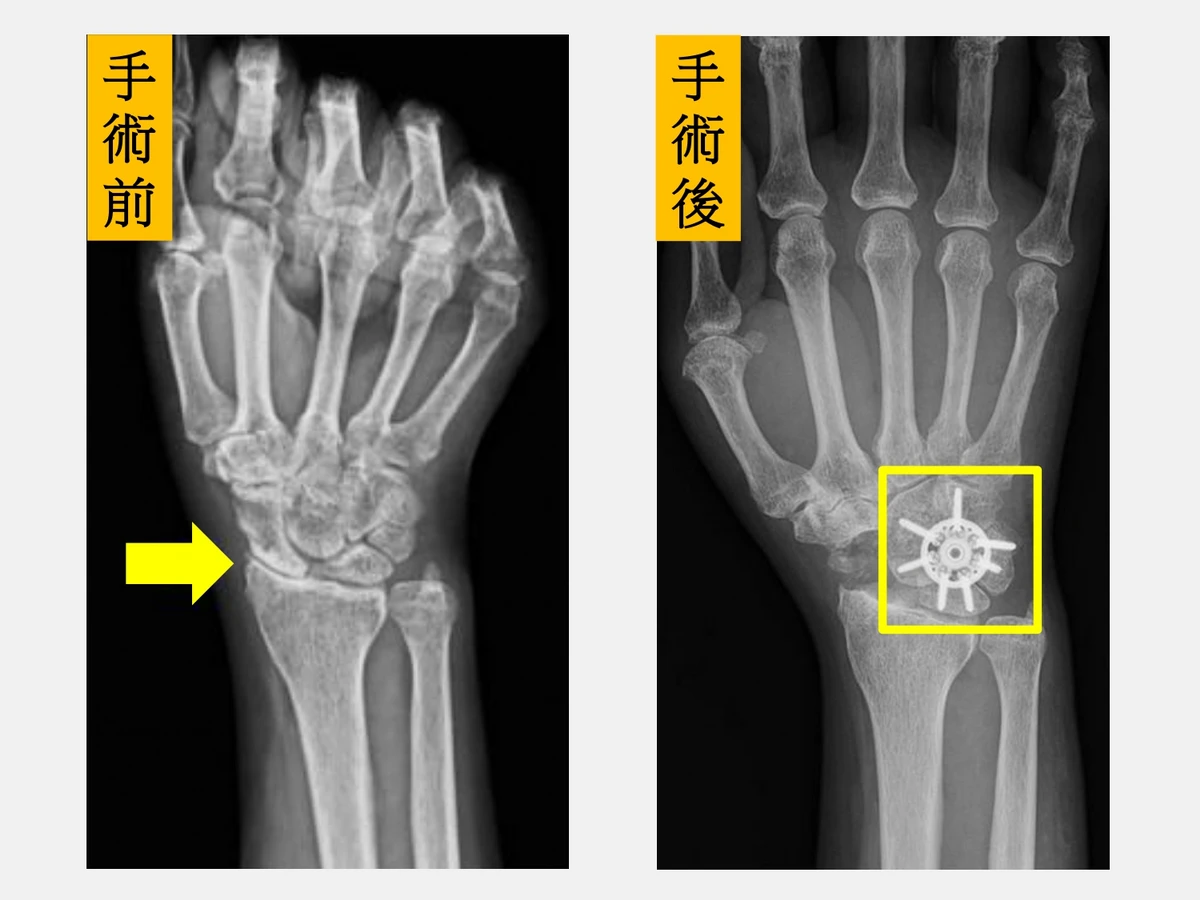

陳重宇表示,由於劉先生的症狀是手腕腫脹、活動受限和握力明顯下降,X光檢查顯示已進展至中後期病程,經醫療團隊充分討論後,劉先生接受「舟狀骨切除合併四角融合術」(scaphoid excision and four corner fusion),並使用新型環狀鋼板固定,復原順利。